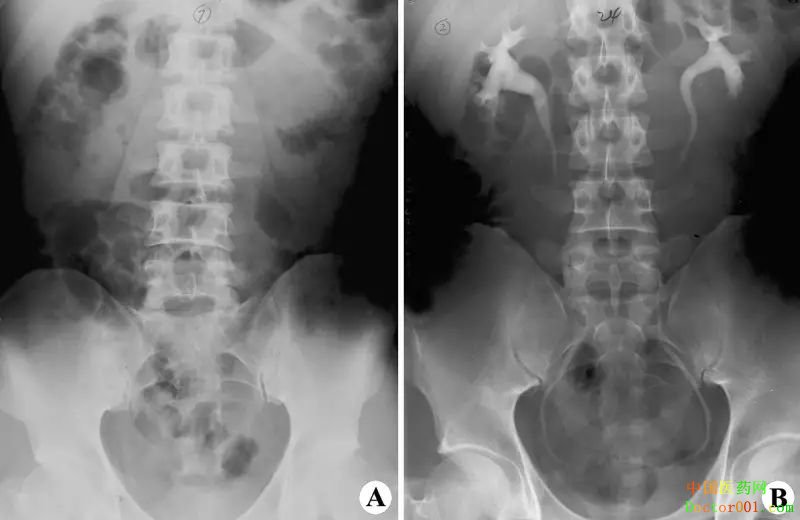

9. 泌尿系及男性生殖系造影:检查前1天的晚餐应吃软食,此后就要禁食。检查前1天的晚上还要服泻药以清除肠腔内的积气、积粪。检查之前要排空小便。 10. 女性生殖系统造影:在检查之前,要排空大小便,未解大便者要灌肠,还要剃除阴毛,清洗阴道。 11. 化验室检查:抽血作生化指标检查时,应在早餐前抽空腹血,这样查出的结果较为准确。尤其是检查肝功、血糖、血脂等项目,对于空腹的要求更为严格。 12. 体检前一天22点前休息,禁食(包括水),空腹8点--10点前到体检中心。